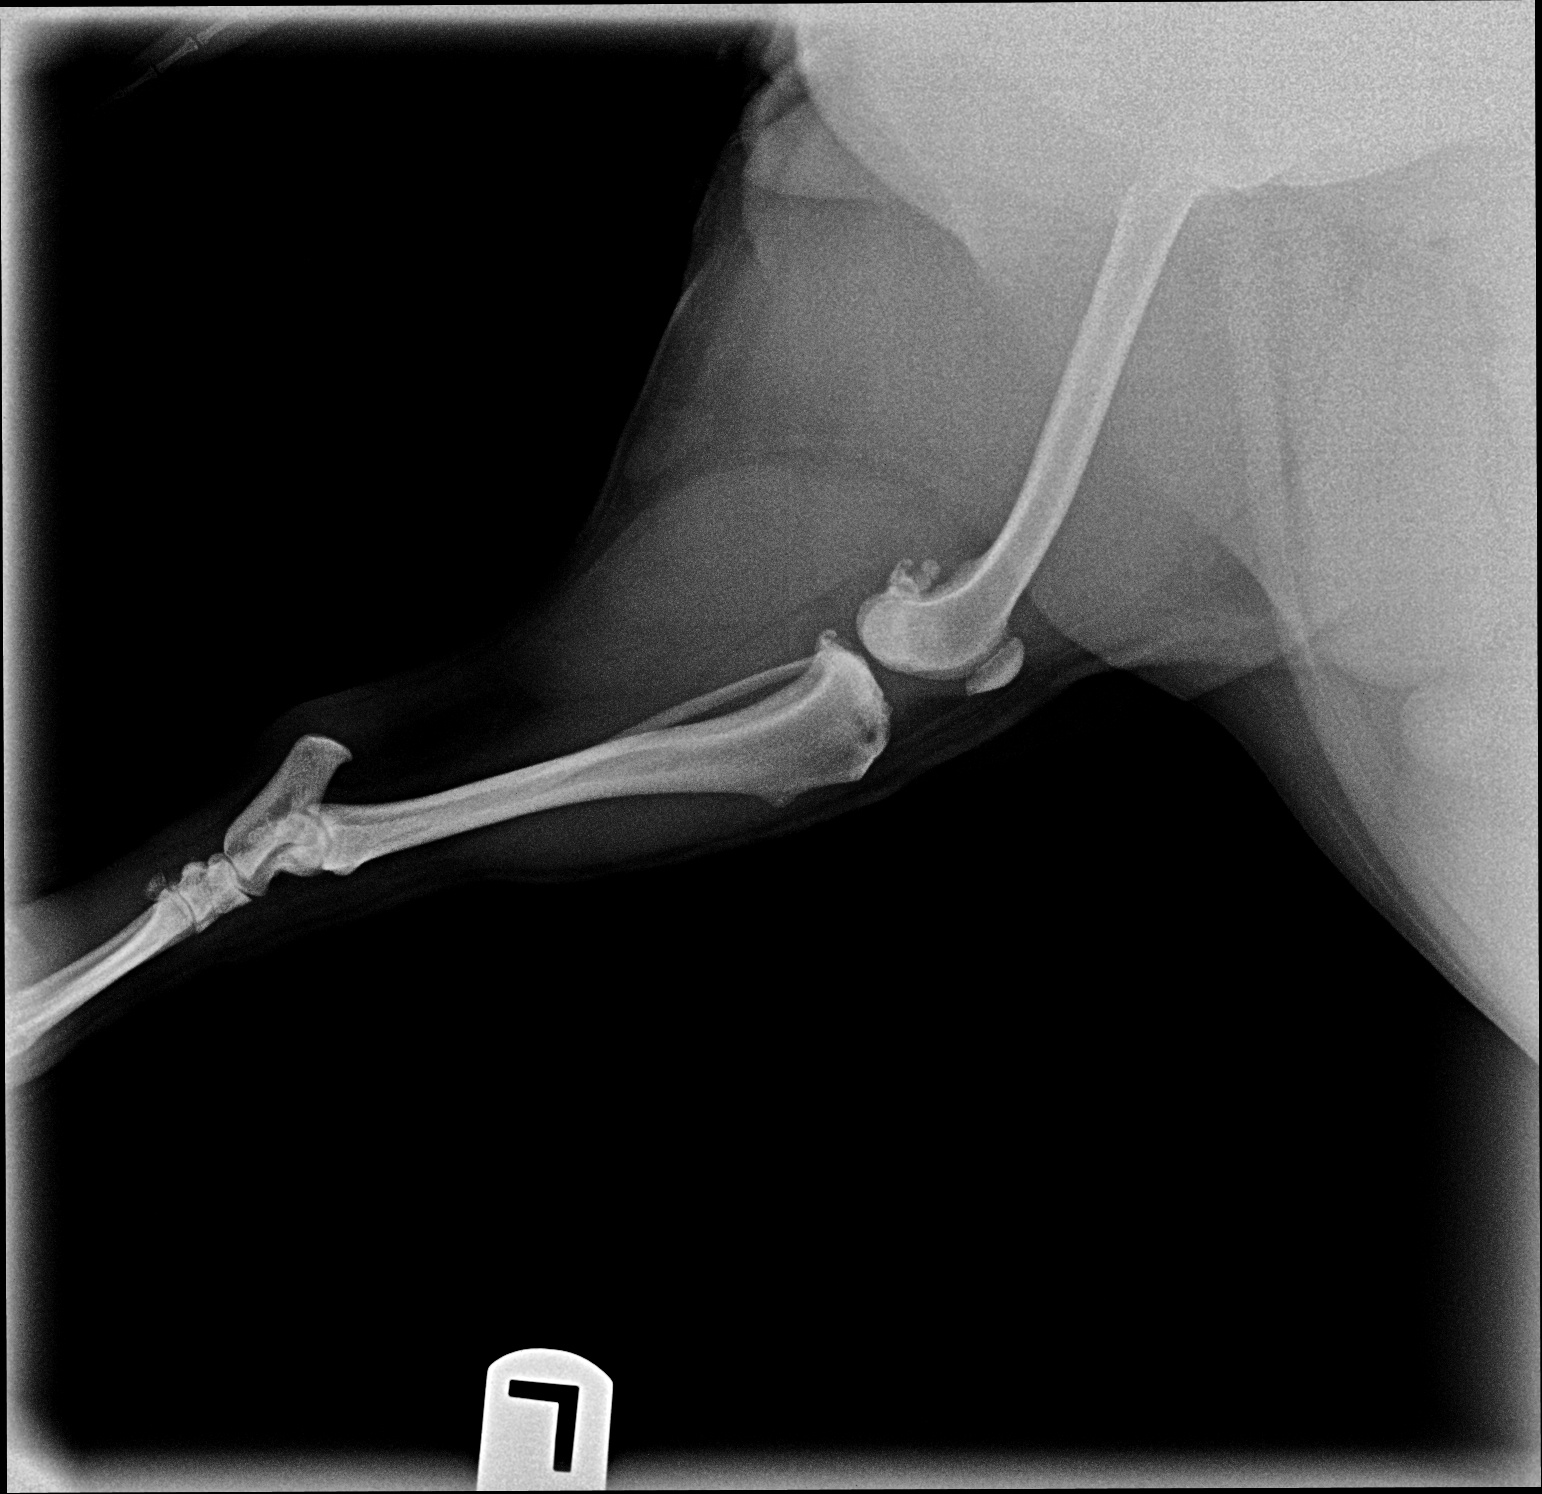

The images from the source dataset had issues and needed to be consolidated into a more usable framework. These issues were mostly due to inconsistencies in practices of radiographers and movement by the animals during radiography that resulted in radiographs with incomplete data, inconsistent image quality, such as varying contrast, brightness and positioning of point of interest or images that failed to meet the prerequisite conditions for this task. Examples of difficult data are shown in Fig. 5.

Most of the source dataset of over a thousand unique knee radiographs were distorted, had poor patient positioning, or were otherwise unfit for annotating. 250 of the original images were of sufficient quality to contribute to this effort. These images were set to have 6 different classes for training purposes, as mentioned and shown in Fig. 4. These were then trained using YOLOv3 [10] and the results of the predicted annotations are shown in Table I. From these predictions the centroids were extracted, which is then used to plot the FTL and MTPL. Then using the method mentioned in Section II, TPA is calculated. Examples of images, the region of interests detection and their respective TPA determination is shown in Fig. 6 and Table I: